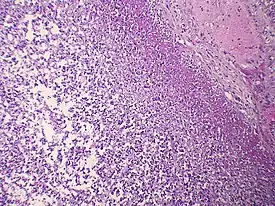

.jpg.webp)